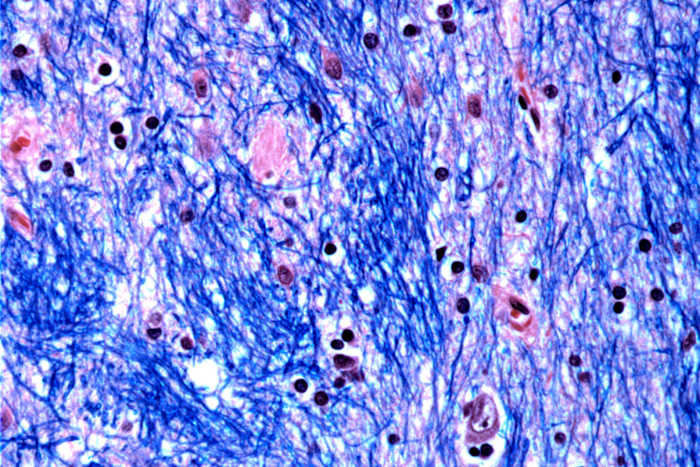

Wetenschappers ontrafelen het mysterie van wat de ziekte van Huntington veroorzaakt, een verwoestende en fatale erfelijke aandoening die toeslaat in de bloei van het leven en ervoor zorgt dat zenuwcellen in delen van de hersenen afbreken en afsterven.

De hersenceldood leidt uiteindelijk tot problemen met bewegen, denken en gedrag. De symptomen van Huntington – waaronder onwillekeurige bewegingen, onvaste gang, persoonlijkheidsveranderingen en verminderd beoordelingsvermogen – beginnen doorgaans tussen de leeftijd van 30 en 50 jaar en verergeren geleidelijk in de loop van 10 tot 25 jaar.

Wetenschappers van het Broad Institute of MIT en Harvard, McLean Hospital in Massachusetts en Harvard Medical School bestudeerden hersenweefsel gedoneerd door 53 mensen met de ziekte van Huntington en 50 zonder de ziekte, waarbij ze een half miljoen cellen analyseerden.

Ze concentreerden zich op de Huntington-mutatie, waarbij een stuk DNA in een bepaald gen betrokken is, waarbij een drieletterige reeks – CAG – minstens veertig keer wordt herhaald. Bij mensen zonder de ziekte wordt deze reeks slechts 15 tot 35 keer herhaald. Ze ontdekten dat DNA-trajecten met 40 of meer van dergelijke ‘herhalingen’ zich in de loop van de tijd uitbreiden tot ze honderden CAG’s lang zijn. Zodra CAG’s een drempel van ongeveer 150 bereiken, worden bepaalde soorten neuronen ziek en sterven ze.